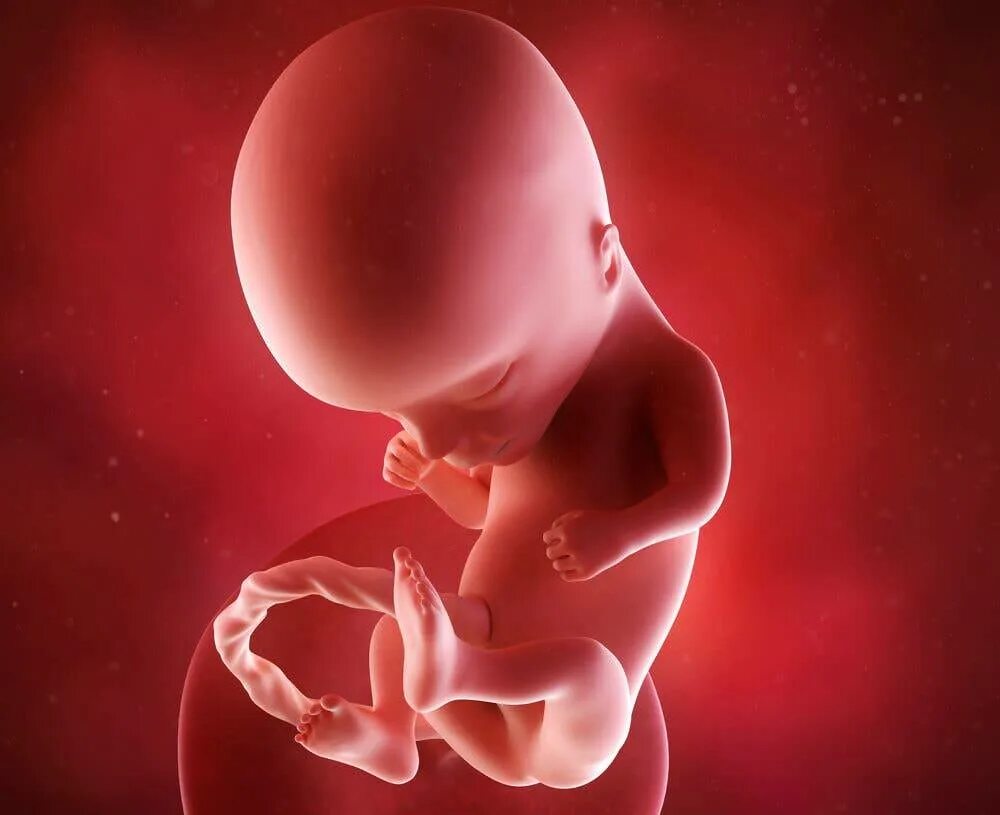

14 неделя ощущение